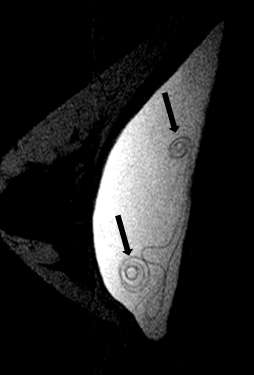

Fully collapsed intracapsular ruptures appear as multiple hypointense curvilinear lines that float within the hyperintense silicone gel, referred to as the “linguine sign” (Figure 4). The floating curvilinear lines represent the collapsed outer shell6.

Figure 4: Sagittal silicone-excited MR with arrows showing hypointense curvilinear lines (linguine sign) (arrows).